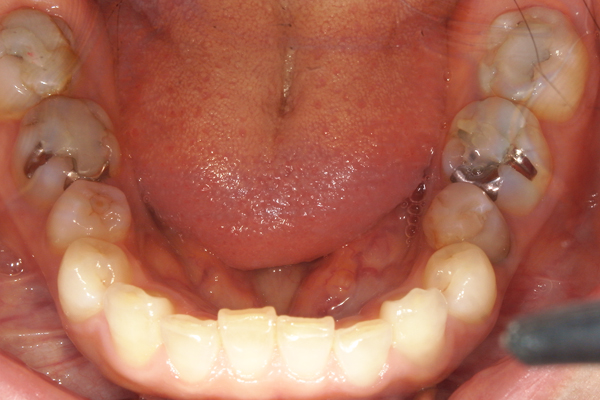

初診時の口腔内写真

奥歯にプラスチックを盛り足しての噛み合わせ治療が施されており、お口全体で噛める状態ではありませんでした。

噛み合わせが深く、前歯が噛めておらず、奥歯の負担が強い状況でした。